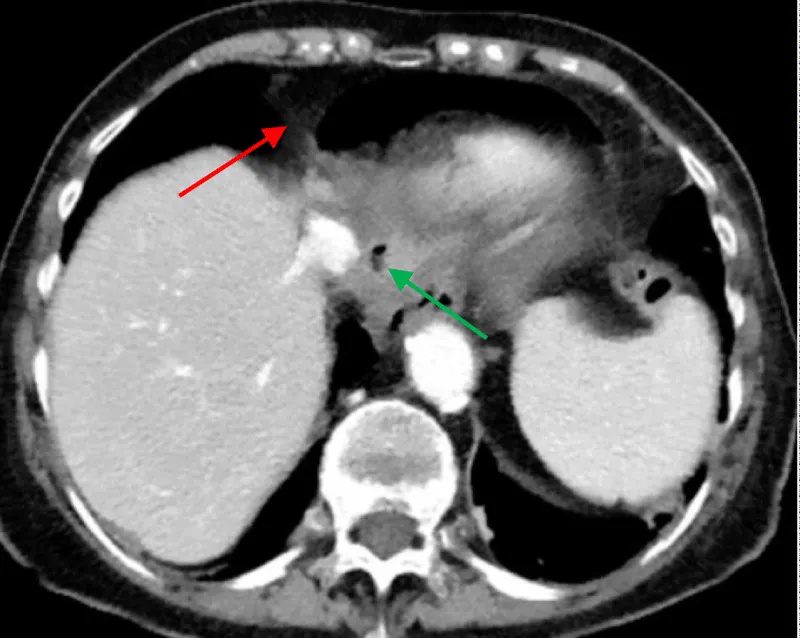

The approval of the hospital’s ethics committee was obtained to present the following case. A 78-year-old female patient was admitted to our hospital with complaints of recurring epigastric pain and diarrhea. The clinical workup revealed collagenous colitis. Upper GI endoscopy was normal. Her medical history included gastroesophageal reflux treated by Nissen fundoplication in 1980 with redo surgery in 2010. While hospitalized, she presented acute retrosternal and epigastric pain not responding to usual medication. Clinical evaluation revealed hemodynamic stability, pericardial metallic tinkling friction rub, mill wheel murmur, and no signs of peritonism. Blood analysis showed a slight inflammation while high-sensitive troponin dosage and leukocytosis were within normal range. Radiologic evaluation by CT scan revealed pneumopericardium associated with a fistula path going from the Nissen’s fundoplication valve towards the pericardial cavity (Figures 1,2).

Figure 1: CT scan showing fistula’s path (red arrow)./p>

Figure 2: CT scan showing pneumopericardium (red arrow) and pathologically edematous Nissen’s valve (green arrow).